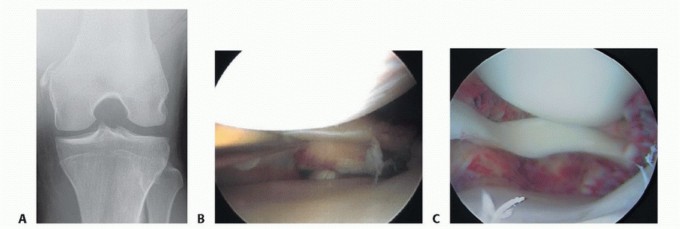

DEFINITION Knee arthroscopy is a minimally invasive video-assisted surgical intervention for intra-articular …